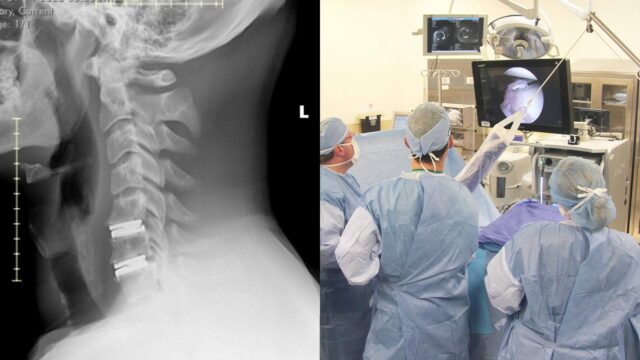

Populárny veterán WWE Ridge Holland, známy ako Luke Menzies, je teraz takmer pripravený začať svoju cestu späť do fitness, aby mohol znova zápasiť. Hviezda to zdieľala online spolu s röntgenom krku a chrbtice a povedala, že bol konečne úplne očistený, aby mohol pokračovať vo fyzickom cvičení bez akýchkoľvek obmedzení, aby mohol správne trénovať. Stalo sa tak po výmene krčnej platničky druhej úrovne, ktorú absolvoval len pred 8 týždňami. Povedal, že vie, že je to neskutočné, a že teraz potrebuje len dostať skrutky z nohy.

„Od dnešného dňa som úplne pripravený vrátiť sa k neobmedzenému fyzickému cvičeniu po mojej dvojúrovňovej výmene krčnej platničky, ktorú som mal pred 8 týždňami… NESKUTOČNÉ. Ďalej potrebujem dostať tieto skrutky z nohy. Môžete ma volať Bionický Yorkshireman! “